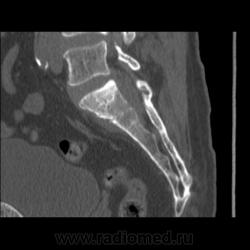

Крестец, КТ. МТС?

Мужчина 53 года. По МРТ экстрамедуллярное образование на уровне L5-S1. Сигнал он S1 изменен... Подозревают МТС. В анамнезе образование почки. Какое - не известно. Ваше мнение?

Всем добрый вечер! Я думаю, что здесь именно деструкция S1 и патологический перелом+мягкотканный компонент.

Обратите внимание на видео, тут еще перелом правой латеральной массы крестца, но туда вроде дрянь не распространяется... Как объяснить? Может, это не мтс?

МРТ делали. Заключение: Экстрамедуллярное новообразование на уровне L5-S1 позвонков со стенозом позвоночного канала и деструктивными изменениями в S1 позвонке.

Тут вся костная ткань какая-то остеопоротичная... По МРТ низкий сигнал по Т1ВИ от тела позвонка и этого паравертебрального компонента... Паравертебральный компонент пишут, что накапливает контрастное вещество. Например, туберкулезный спондилит не укладывается в это? А просто спондилит? А миеломная болезнь?

Т.е. диски интактны, не отечны, значит и спондилит исключается. Следовательно об*емный процесс, а первичный или вторичный на 100% ответит только биопсия, мы можем лишь предполагать.

Метастазы.